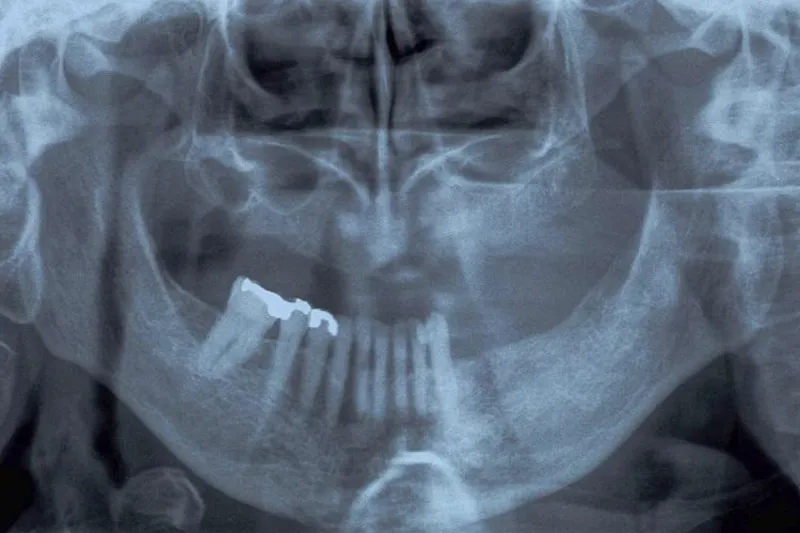

Klinisk og radiologisk undersøgelse (enoral, oversigtsrøntgen eller scanning) med henblik på diagnosticering af odontogent fokus.

Billeddiagnostik. Enorale røntgenoptagelser, panoramaoptagelse, CBCT.